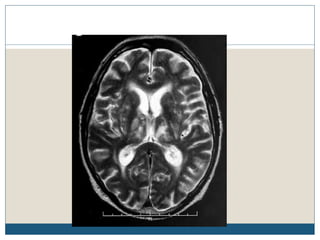

Typical MRI lesions

 Trident shaped / spreading bushfire pattern in central pons

 Signal characteristics of affected region include:

 T1: mildly or moderately hypointense

 T2: hyperintense, sparing the periphery and corticospinal tracts

 FLAIR: hyperintense

 DWI: hyperintense

 ADC: signal low or signal loss

 T1 C+ (Gd): usually there is no enhancement

 Radiologic findings do not improve over time, despite complete or nearly complete

clinical recovery

Typical MRI lesions Trident shaped / spreading bushfire pattern in central pons  Signal characteristics of affected region include:  T1: mildly or moderately hypointense  T2: hyperintense, sparing the periphery and corticospinal tracts  FLAIR: hyperintense  DWI: hyperintense  ADC: signal low or signal loss  T1 C+ (Gd): usually there is no enhancement  Radiologic findings do not improve over time, despite complete or nearly complete clinical recovery

Radiological differential diagnosisof CPM  General imaging differential considerations include:  demyelination - multiple sclerosis (MS)  infarction from basilar perforators can be central  pontine neoplasms - astrocytomas